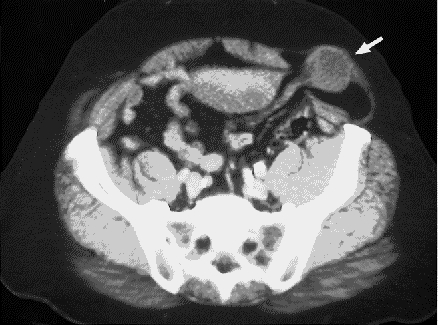

A preoperative diagnosis of diverticulitis was entertained and a CT image of the abdomen requested (Fig. 1).

FIG. 1. Abdominal computed tomographic image of patient with left-lower quadrant pain and nausea.

The CT image demonstrates a Spigelian hernia in the left lower abdomen (Fig. 2). A loop of bowel is visibly herniated through the linea semilunaris and contained within the external oblique aponeurosis. At surgery, a paramedian incision was made over the mass. An incarcerated, strangulated loop of small intestine was found herniated through a 2 cm х 2 cm defect along the linea semilunaris. Approximately 20 cm of small intestine was resected, with primary anastamosis. The defect was closed with primary suture repair. The patient's postoperative course was uneventful.